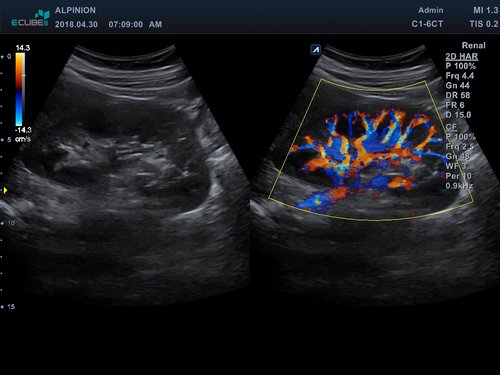

• C1-6CT (1-6 MHz) für Ultraschalluntersuchungen in Bereichen Abdomen, Geburtshilfe, Gynäkologie, fetales Echo

• Farbdoppler: farbige Darstellung der Richtung des Blutflusses

• Powerdoppler: sensitive, farbige Darstellung des Blutflusses unabhängig von Geschwindigkeit und Richtung

• DPDI: Technologie, die Sensitivität des Powerdopplers mit der Flussrichtungsinformation des konventionellen Farbdopplers kombiniert